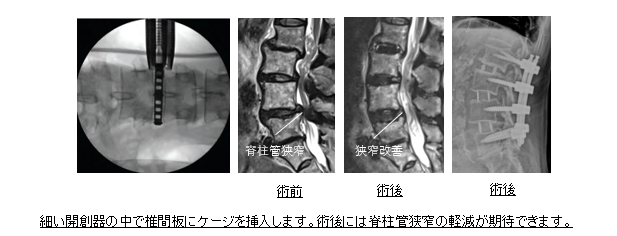

側方侵入腰椎椎体間固定術(eXtreme Lateral Interbody Fusion:XLIF)

適応:腰部脊柱管狭窄症, 腰椎変性すべり症、変性側弯症、腰椎分離症など

この術式は椎間板を取り除いてケージ(背骨を安定させるスペーサー)を設置する方法です。以前は大きな皮膚切開が必要でしたが、開創器や光源の進化により、数センチの傷で手術が可能となりました。日本では2013年に導入され、認定を受けた施設でのみ施行が許可されています。本術式では大きなケージを挿入できるため、曲がった背骨を矯正しやすいなどのメリットがあります。また側腹部から椎間板にアプローチすることで背筋を損傷することがなく、体への負担が少ないのが特徴です。適応となる病態には、この術式を選択しています。術後2日より歩行を開始し、2〜3週間で歩行が安定すれば退院が可能となります。